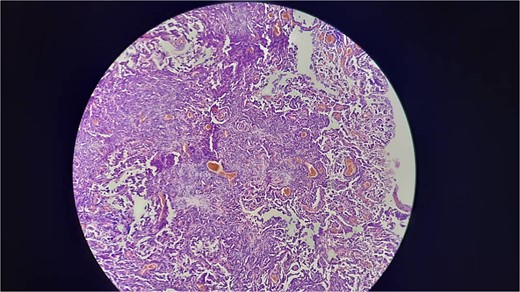

A 38-year-old male educator and part-time farmer with no notable cancer history in his family and a non-smoking background sought medical attention. His medical records included a left inguinal hernia repair two years prior and an ischemic stroke six years ago, for which he was undergoing ongoing treatment with clopidogrel, aspirin, and rosuvastatin. The patient reported swelling in the right inguinal region, without any other symptoms. The patient was prepared for surgery to repair the hernia. Upon opening the hernial sac, a thickened wall was observed. Aspiration was conducted to exclude bladder involvement, yielding cloudy, serous fluid indicative of ascites and omental thickening. Based on these observations, samples from the hernial sac wall (peritoneum), omentum, and ascitic fluid were submitted for histopathological analysis, and the hernia was repaired (Fig. 1). Peritoneal surgical biopsy showed that the peritoneal tissue fragments involved epithelioid cell malignant neoplasms with tubular and papillary formations and stromal infiltration. An IHC study revealed Calretinin and CK5/6 markers (mesothelial cell markers) were diffusely positive in the tumor, leading to a diagnosis of malignant mesothelioma. (Fig. 2 and 3) CEA levels were assessed and found to be within the normal limits. Contrast-enhanced computed tomography (CT) of the chest, abdomen, and pelvis revealed a 58 × 31 mm lobulated mass with multiple septate cavities in the lateral and basal pleura of the left lower lobe (Figs 4–6). The scan also showed thickening of the omentum, mesentery, and peritoneum, consistent with a left pleural mesothelioma with peritoneal and omental metastases. Oncologists diagnosed the patient with stage 4 pleural mesothelioma. The patient was determined to require oncological treatment consisting of eight cycles of cisplatin combined with gemcitabine. Unfortunately, the patient died during the fourth chemotherapy cycle.

Shows that invasive proliferation of atypical mesothelial cells with large hyperchromatic nuclei with tubulpapillary and solid growth pattern.